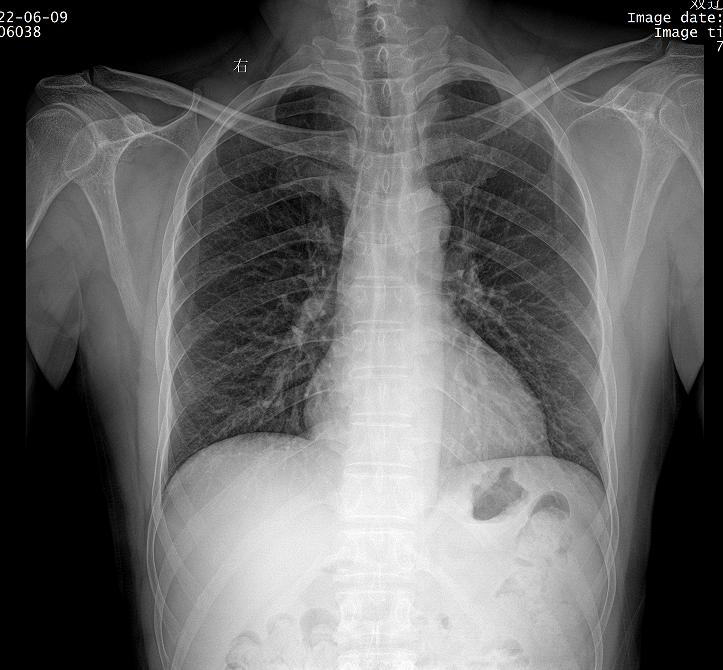

智能AI骨抑制功能,肺纹理和病灶完整保留还原真实场景,快速诊断肺部病灶

胸部摄影 四肢摄影